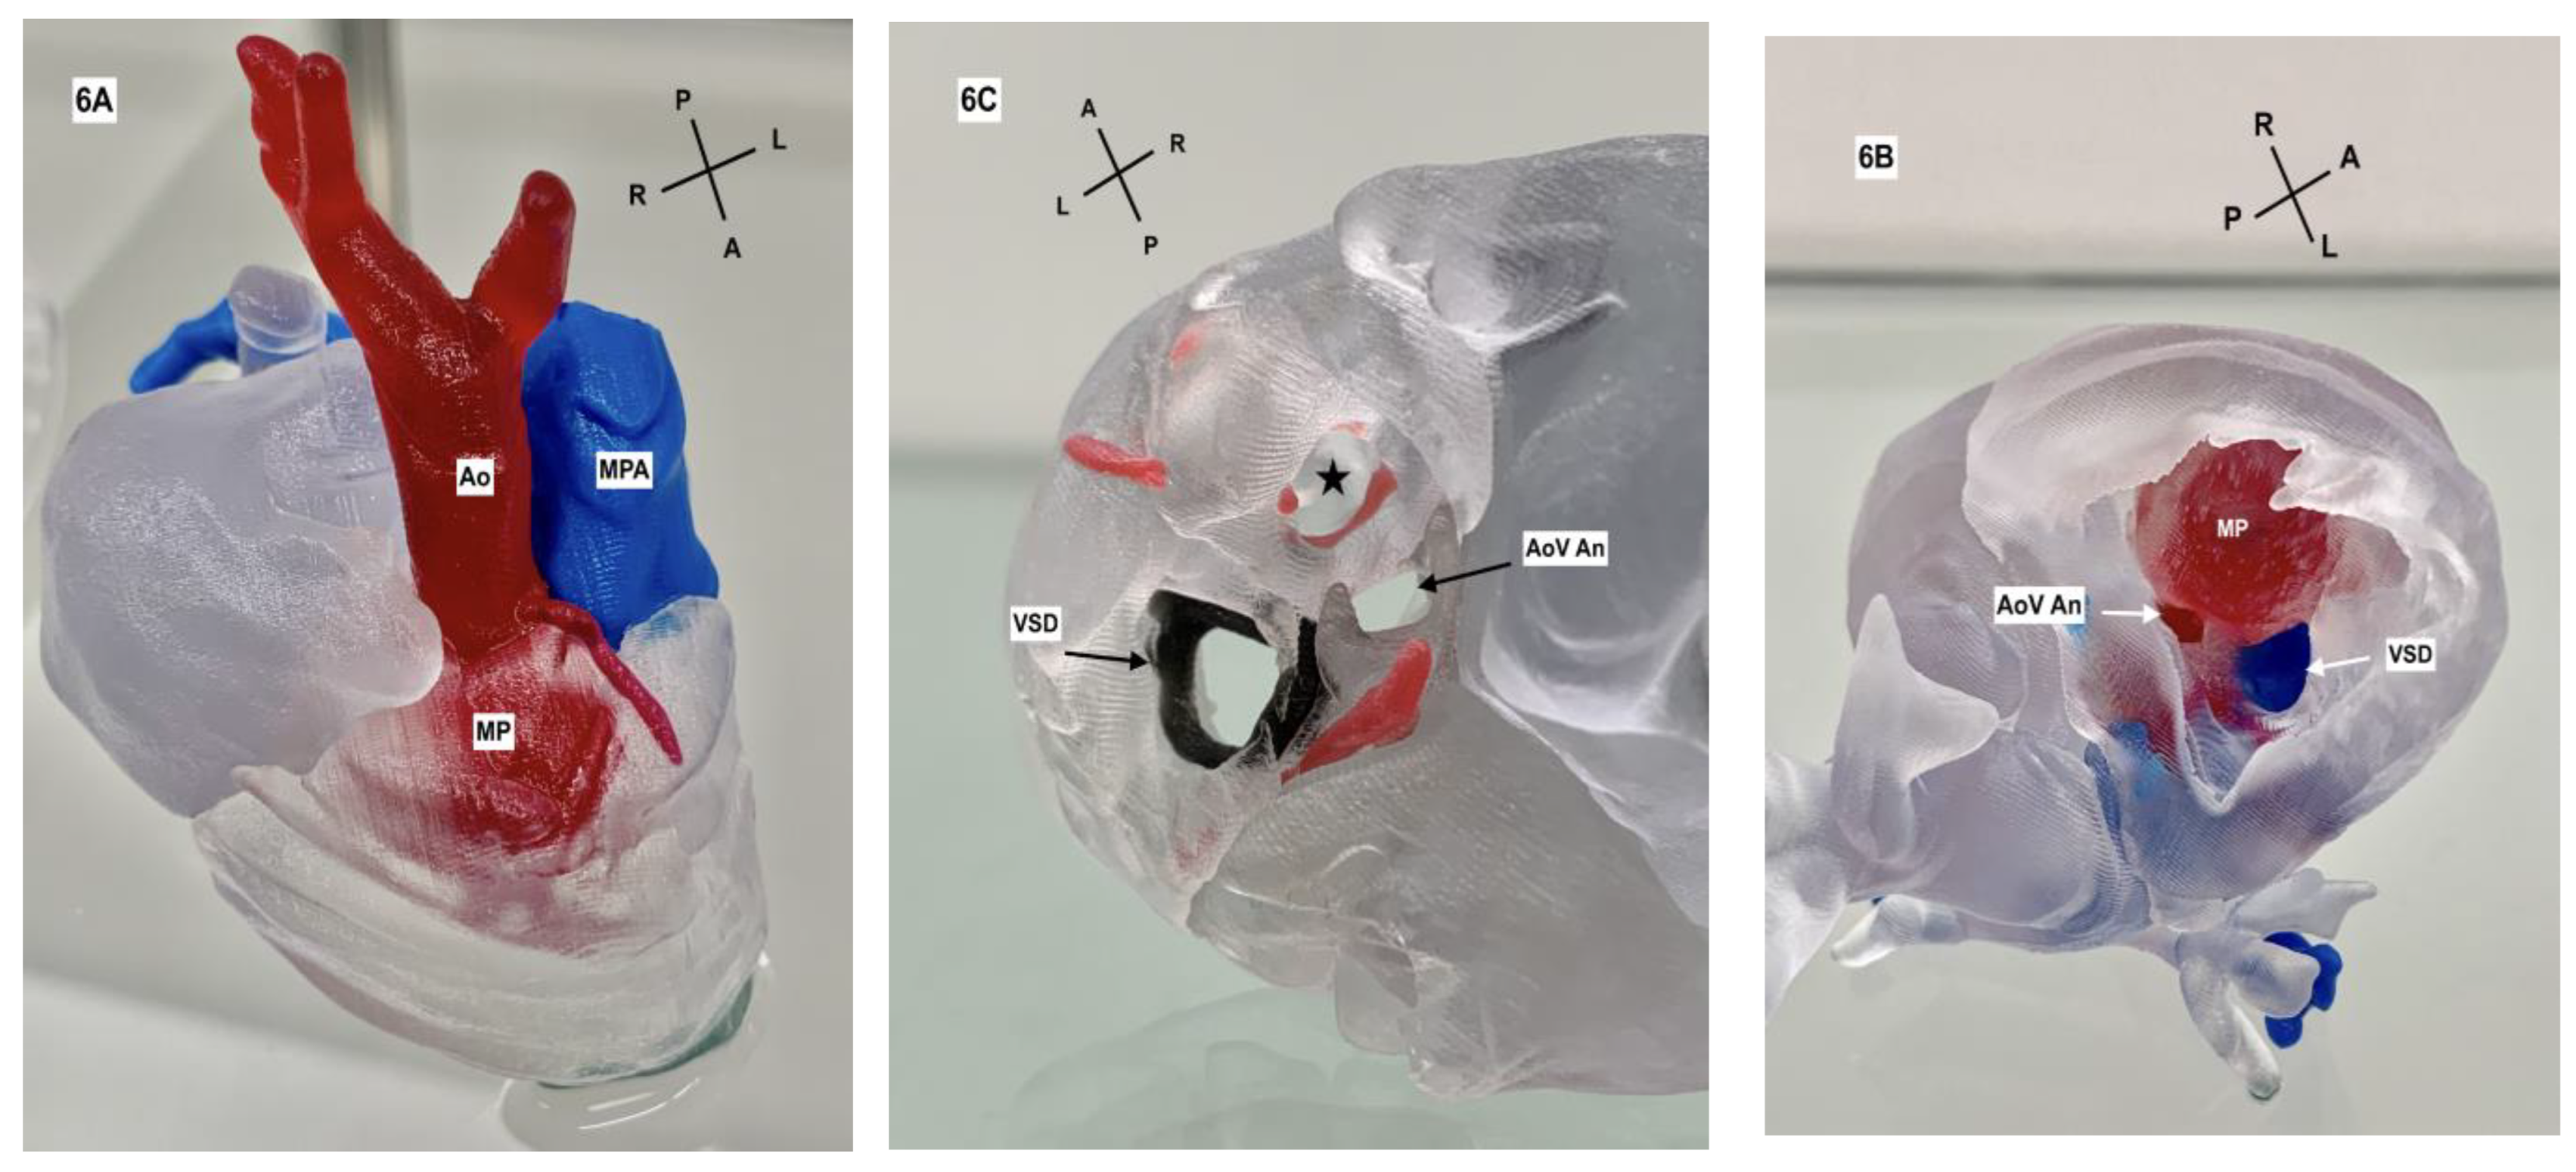

2. Case Description